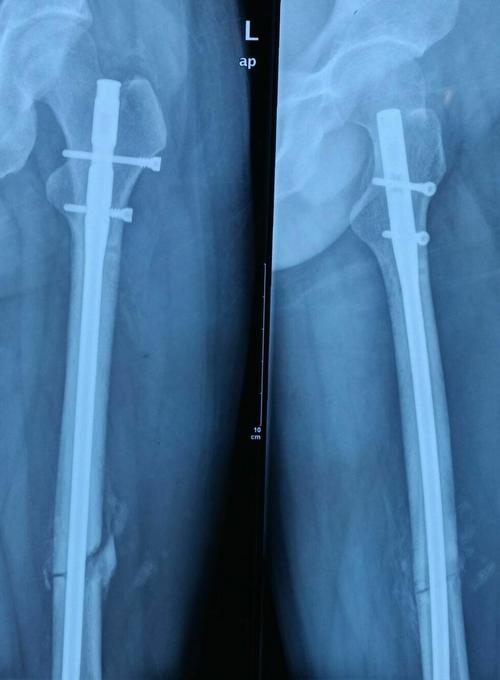

其它 刘威的美篇 写美篇贺**,女,左股骨干中段骨折,行股骨干骨折闭合

逆行髓内钉治疗双侧股骨干骨折

股骨干骨折闭合复位髓内固定